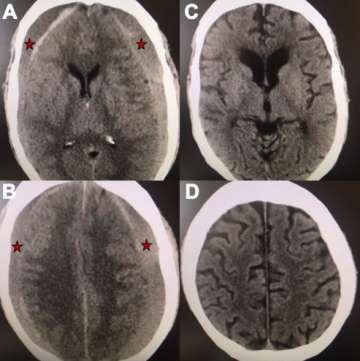

Middle Meningeal Artery Embolization – This procedure is performed in an endovascular suite with the patient asleep under general anesthesia. The endovascular surgeon uses minimally invasive technique to enter the blood vessels in the arm or leg and then advances small tubes called catheters through the arteries under x-ray guidance to the middle meningeal artery on the side of the subdural hematoma. The middle meningeal artery is located on the underside of the skull (outside of the brain) but also provides blood supply to the abnormal membranes that surround the hematoma and contribute to hematoma growth (Figure 2). Under fluoroscopic guidance, the surgeon delivers a specially made liquid glue material (called nBCA or Onyx) or small particles through the small tube and permanently blocks the middle meningeal artery. Platinum micro-coils can be used as well. After the procedure, the tubes are removed and the small puncture site in the arm or leg artery is closed. In the weeks following the procedure, there is reduced bleeding from the subdural hematoma membranes and the hematoma collection slowly shrinks in size and often goes away completely over the course of several months (Figure 3).

Figure 3. A, B) Axial views of a brain CT scan demonstrating chronic subdural hematomas on both sides of the brain compressing it inwards (red stars mark the hematoma). C, D) Axial views of a CT brain of the same chronic subdural hematoma 3 months after Middle Meningeal Artery Embolization demonstrating resolution of the chronic subdural collection on both sides.- Burr hole Drainage – This is the most common surgical procedure for treatment of chronic subdural hematomas and is performed in the operating room with the patient under general anesthesia. The procedure involves opening two holes, each about the size of a quarter, in the skull to evacuate (drain) the hematoma. A drain is often left in the hematoma space for several days after surgery to maximize the drainage.